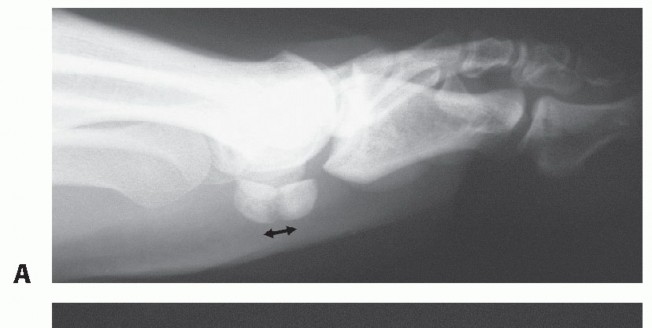

Foot deformities that concentrate pressure to the sesamoids increase the chance of suffering sesamoid stress fractures in both athletic and nonathletic persons. Cavus foot deformities with a steep plantarflexed first ray stress both sesamoid bones. Hallux valgus deformity with varus dislocation of the metatarsal head leads to

pressure concentration at the medial sesamoid bone only11,12 (FIG 2).

FIG 2 • Biomechanics of the sesamoid complex in hallux valgus deformity. A. Varus subluxation of the first metatarsal bone causes pressure concentration to the medial sesamoid bone. The intersesamoid crista enhances friction to the sesamoid joint surface. B. After stress fracture occurs, hallux deviation will cause constant fragment displacement. Therefore, immobilization may not suffice. Sesamoid excision will enhance hallux deviation if the deformity is not addressed. (From Pagenstert GI, Valderrabano V, Hintermann B. Medial sesamoid nonunion combined with hallux valgus in athletes: a report of two cases. Foot Ankle Int 2006;27:135-140.)

Foot deformities can cause fragment separation and may prevent healing with immobilization.11

A complete examination of sesamoid status includes examination of the whole foot and ankle, with special

attention to cavus deformity with a flexed first ray or hallux valgus deformity11 (see FIG 2B).